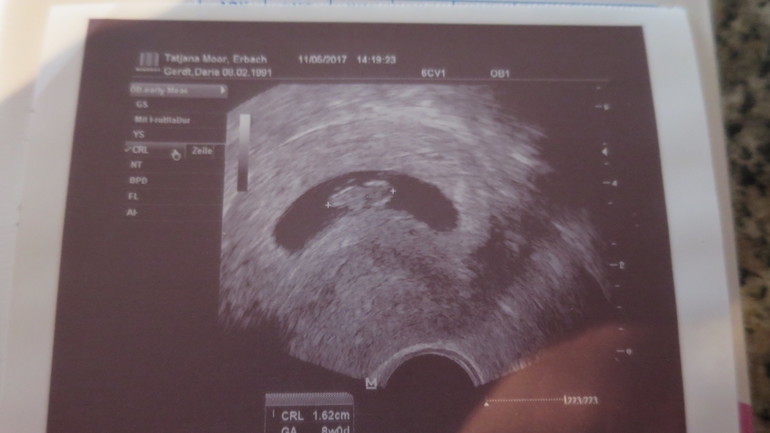

УЗИ, КТГ, доплерСегодня была на УЗИ, у нас все отлично, растет наша бусинка и развивается. Рост уже 1,62 см....за 2 недельки вырос.....на первом узи был 0,8 мм. По УЗИ ровно 8,0 нед. СБ+ . Сразу поставили на учет, и 3 банки крови выкачали) Сделали термин на скрининг на 12 июня!!!!

Расти бусинка